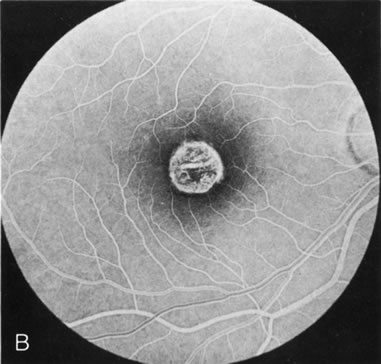

Dye leakage in RP may occur from the retinal vessels or at the level of the retinal pigment epithelium (Fig. 1B).2–4 The leakage may be seen in the macula and posterior pole, along the vascular arcades in the distribution of the radial peripapillary capillaries, and in the periphery (where an exudative vasculopathy resembling Coats' disease is suggested).

Of more clinical importance is the role of FA in the diagnosis and treatment of cystoid macular edema (CME) (Fig. 1C and D). Stereoscopic FA indicates that the leakage, which may be diffuse or have the typical petaloid stellate appearance of CME, can come from the perifoveal retinal capillaries, from the choroid through the RPE, or from a combination of both sources.4 With the recent suggestion that CME in RP may be successfully treated with acetazolamide,5, 6 FA is thus important to document the diagnosis of CME, establish the origin(s) of leakage, and follow patients during and after therapy.